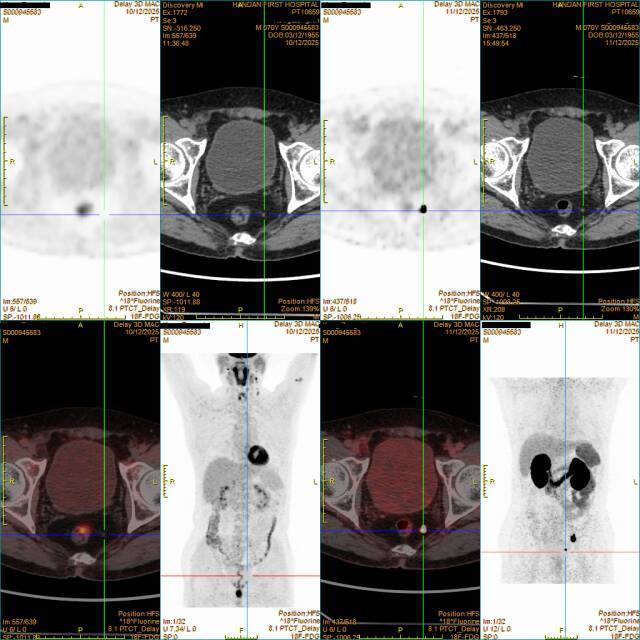

(左四 右四)

70岁的孔先生在前列腺癌切除术后2月余来我院进行复查。PSMA PET/CT(右4图)凭借“明察秋毫”的技术优势,在直肠旁发现一个直径仅0.3厘米的微小转移病灶,而FDG PET/CT(左4图)完全遗漏了这一病灶。在患者术后PSA尚未显著升高的关键阶段,PSMA显像实现了极早期的生化复发及微小转移灶检出,为后续挽救性放疗或靶向治疗赢得了宝贵的“黄金时间”。康复后的孔先生感慨道:“没想到这么小的病灶都能被精准发现,正是这份及时的诊断,给了我康复的希望,邯郸市第一医院的技术值得信赖!”